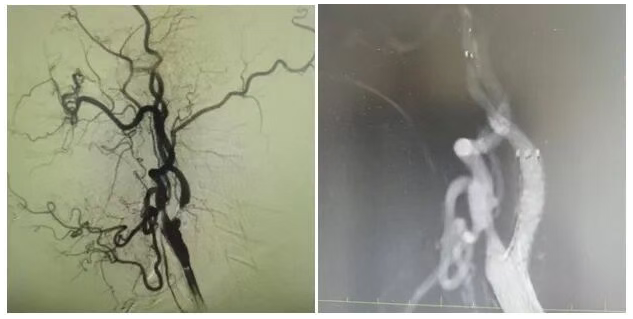

為明確病因,團(tuán)隊(duì)為姜大爺安排針對(duì)性檢查:頭顱 MRI 彌散成像顯示左側(cè)大腦半球有分水嶺性腦梗死,提示腦組織缺血損傷,頸部 MRA 檢查發(fā)現(xiàn)左側(cè)頸內(nèi)動(dòng)脈起始處重度狹窄,血流信號(hào)減弱。隨后的 DSA(數(shù)字減影血管造影)檢查進(jìn)一步明確,左側(cè)頸內(nèi)動(dòng)脈起始處狹窄程度超 90%,呈 “閉塞前改變”,血流受阻導(dǎo)致左側(cè)大腦半球供血不足,進(jìn)而引發(fā)腦梗死與抽搐。

手術(shù)當(dāng)天,丁金明主任親自操刀,團(tuán)隊(duì)默契配合:在姜大爺右側(cè)腹股溝穿刺股動(dòng)脈置入動(dòng)脈鞘,沿鞘送導(dǎo)絲和導(dǎo)管,在 DSA 引導(dǎo)下穿過(guò)狹窄部位,用球囊預(yù)擴(kuò)張后,精準(zhǔn)釋放頸動(dòng)脈支架。術(shù)后 DSA 顯示左側(cè)頸內(nèi)動(dòng)脈血流通暢,狹窄解除。手術(shù)歷時(shí) 1 小時(shí),姜大爺生命體征平穩(wěn),無(wú)并發(fā)癥。